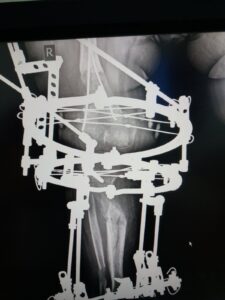

You can see the results of the treatment on the video. This was on January 2nd last year. When we looked and saw that the lengthened bones had grown properly and then we took off Ilizarov’s apparatus. It was necessary to wear the plaster for a certain time, so that the patient could use her leg without any fear. Also, to start walking in the period from when we removed the device until this examination. In the future, she should do exercise for the knees, ankle, and to strengthen her muscles.

And now you were wearing this Ilizarov apparatus, was it hard?

Elma: “Well, it is, it’s quite hard, a little annoying.”

Are you going to keep wearing Ilizarov now or are you done with him?

Elma: “I have another leg extension operation and then I will wear it the most.”

The right doctor was found in the Atlas Hospital in Belgrade. Dad Nusret showed us a picture where you can see how big the problem was with Elma’s legs. They were in the shape of the letter O, and in the case of the left, the deformity was greater because the bone in the axis was completely inverted. After the operation and wearing the apparatus they are corrected now and parent’s happiness is endless. Every inch was important to them.